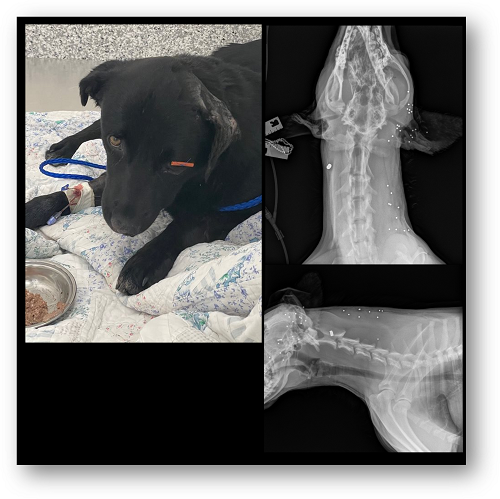

Sid (Garth) came to us after suffering horrific abuse; his body was littered with ammunition, including a .22 shell, three pellets, and a large swath of shotgun blast. His left eye was damaged due to the shotgun pellets, leaving him with irreparable damage and in a severe amount of pain. His left ear was also severely hit, leaving shot wounds in his ear, but thankfully, it could be cleaned and wrapped for recovery.

Our Shelter Medical Center provided an enucleation surgery to remove Sid’s injured eye, allowing him to be more comfortable and live a pain-free life. Sid now has a new lease on life; we will be transferring him back to Friends Furever Animal Rescue for adoption. Learn more…